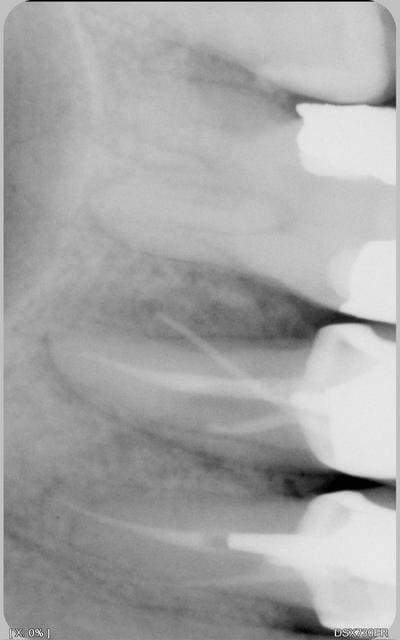

couronne posée il y a 1.5 ans. pas de pb particulier au niveau de douleur a la percussion,mobilité... pas de gonflement,mais une fistule s'est formée en vest de la 25(le cone de la radio qui va sur le coté) que faire? ab, 48 heures après la fin, rebelotte. curetage peri appical? caa marché 8 jours. et pourtant le patient n'a pas mal, juste ce bouton a la con qui est apparu qd la couronne s'est décollée.le ttmt a été refait avant la pose

la radio bis

Je ne suis qu'une AD mais petite idée : la dent ne s'est pas fracturée dans l'axe du cône? C'est peut être ce qui a provoqué le descellement de la couronne, surtout que le pivot à l'air aussi dans l'axe du cône.

Tu es sûr que c'est une fistule et pas un problème dermato ? Ton cône, si il est bien placé, semble pointer sur le néant. Sur quelle longueur approximative s'enfonce-t'il ?

le sondage paro ne donne rien pas de perte d'attache. pas de sensations de fêlures au toucher.pas de douleur en acrasant. couronne non mobile et dent idem.le decollement du lambeau a montré une cavité beante entre 25 26

1°) Le canal que tu a traité me semble un peu court niveau obturation. As-tu réalisé ta LT avec un localisateur d'apex ?

2°) Tu as presque fait une perforation...

3°) Tu as un deuxième canal non traité.

Je m'explique sur ce dernier point :

Ton obturation n'est pas centrée par rapport aux limites externes de ta racine --> donc il y a un deuxième canal.

Celui que l'on voit (traité à 1/2), me semble trop excentré pour être le "vrai" deuxième canal.

NB : il se peut aussi que tu sois face à un seul canal en 8 et que tu n'ais obturé qu'une partie.

le pepin est au niveau du 1/3 moyen. la couronne n'est pas plus débordante que celle des copains.

ce que j'ai vu en decollant la gencive est qu'il y a une cavité beante en 5 et6.

Je crains le pire: 2 canaux vestibulaires, comme le laisse supposer l'orientation du tiers coronaire du canal partiellement obturé, de même que sur la 4...

Cette variation anatomique est possible.

Il serait judicieux de varier les incidences sur d'autres clichés, voire même de comparer avec les homologues si par chance elle ne comportaient pas de traitement canalaire, afin de "détacher" les canxu MV et DV sur l'image en incidences distale puis mésiale, voire individualiser les apex en incidence semi-occlusale? (pardon pour la terminologie à peu-près-iste)